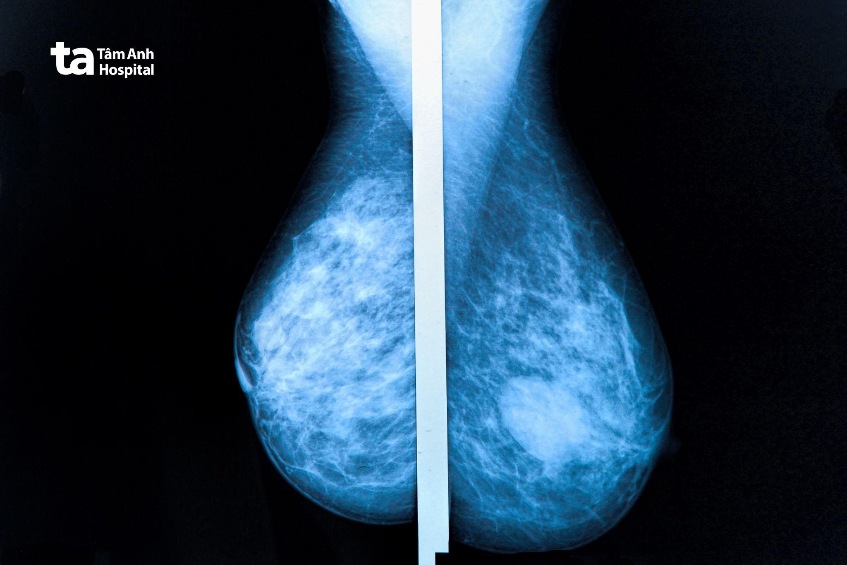

Nếu bạn cảm thấy có khối u hoặc nhận thấy những thay đổi ở vú, hãy đi khám ngay. Bác sĩ sẽ chỉ định một hoặc nhiều xét nghiệm sau: